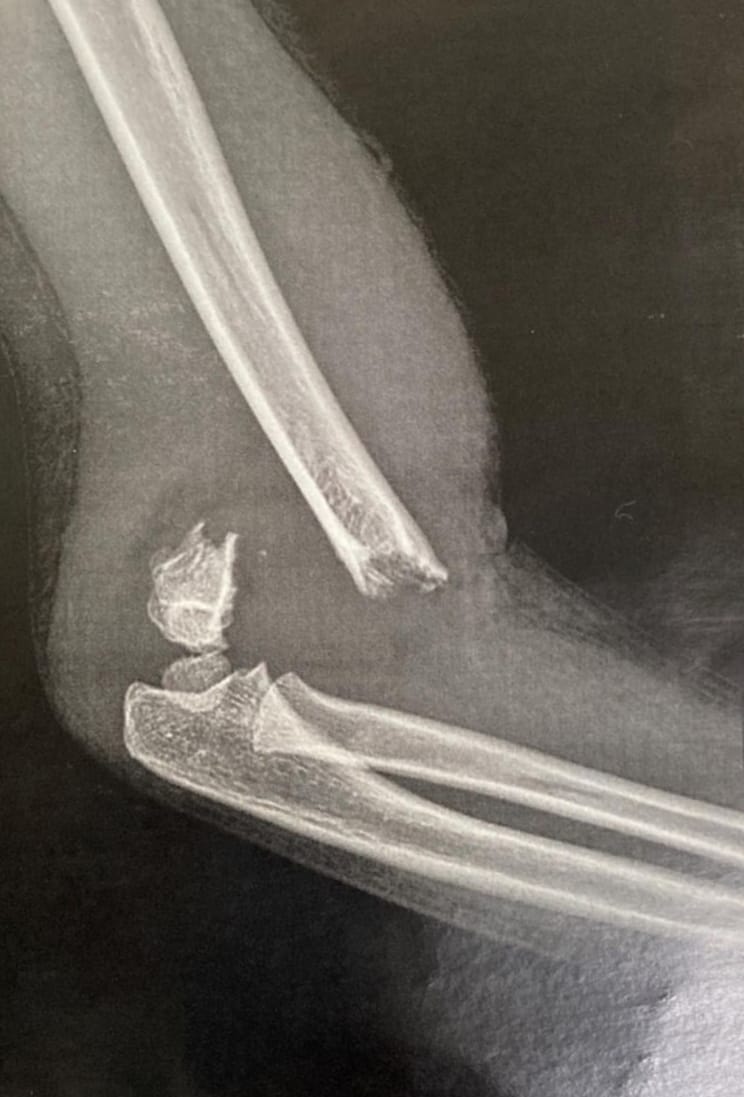

- Compound fractures

- Intra-articular fractures

- Complex fractures

- Open reduction and internal fixation